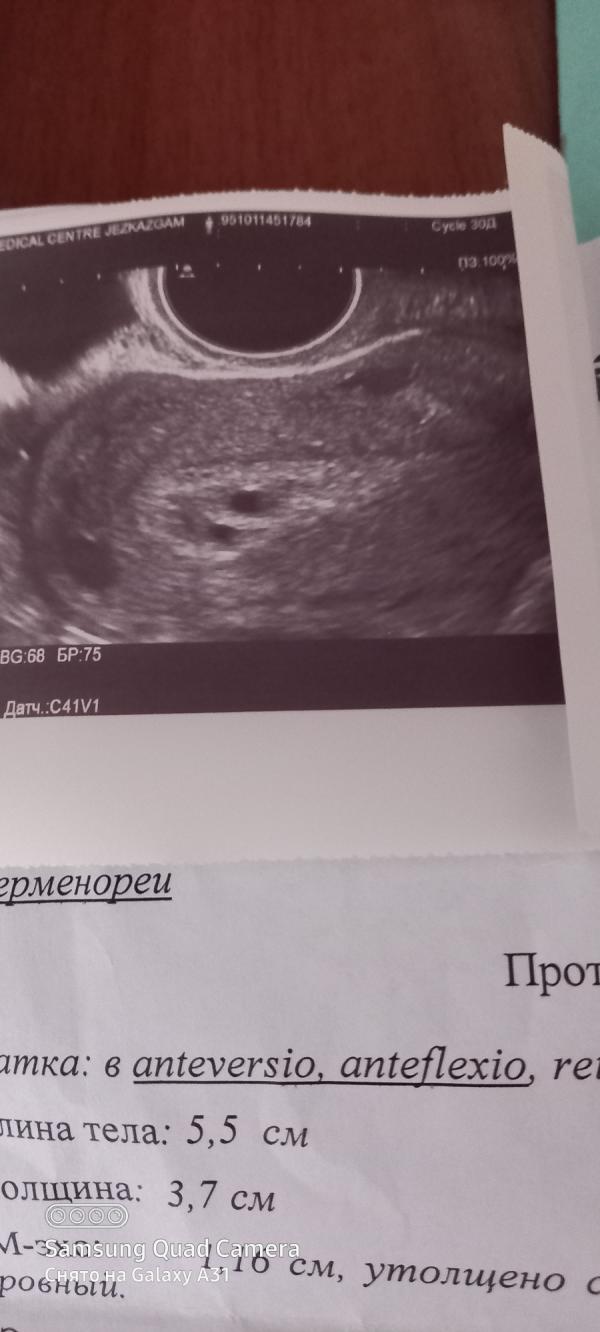

Девочка у кого было железост гиперплазии эндрометрия?? Как лечились, после этого смогли родить??? Очень волнуюсь 😪😪😪